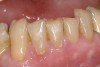

Figure  9  A Class V non-carious cervical lesion.

Figure  10  The Class V lesion restored with self-adhesive resin-based composite.